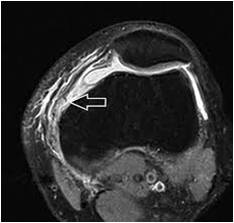

← Patella dislocation – MPFL tear

By Sujit Jos | Published November 24, 2022 | Full size is 234 × 223 pixels Picture1-1 MRI-MPFL-tear Bookmark the permalink.← Patella dislocation – MPFL tear